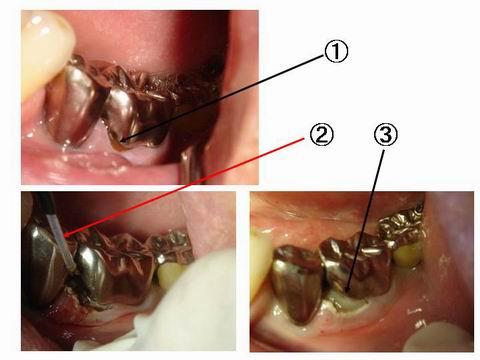

上の写真は、かぶせ物の境目にできた虫歯の治療に使用しているところです。?の部分を治療するのですが、歯茎の下のほうに虫歯が進んでおり、きちんとつめるには、冠を作り直すか、歯茎を切除して治療するか、、、、になります。 ?は、レーザーで歯茎を蒸散させているところで、?が、つめて直したところです。従来の電気メスと違い止血効果も高く、何より傷の回復が早いのが特徴です。